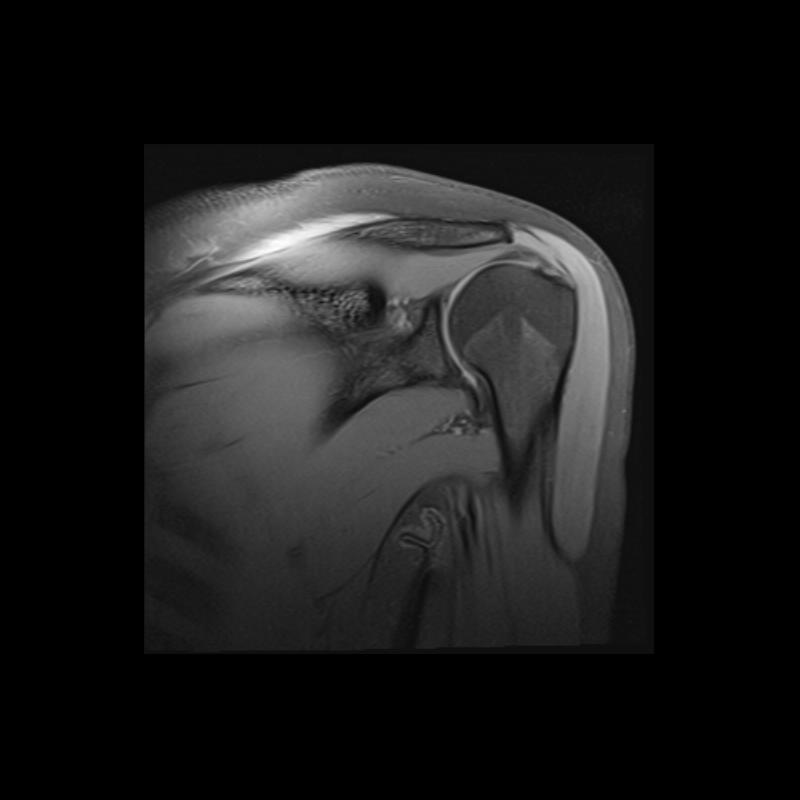

Shoulder MRI Anatomy